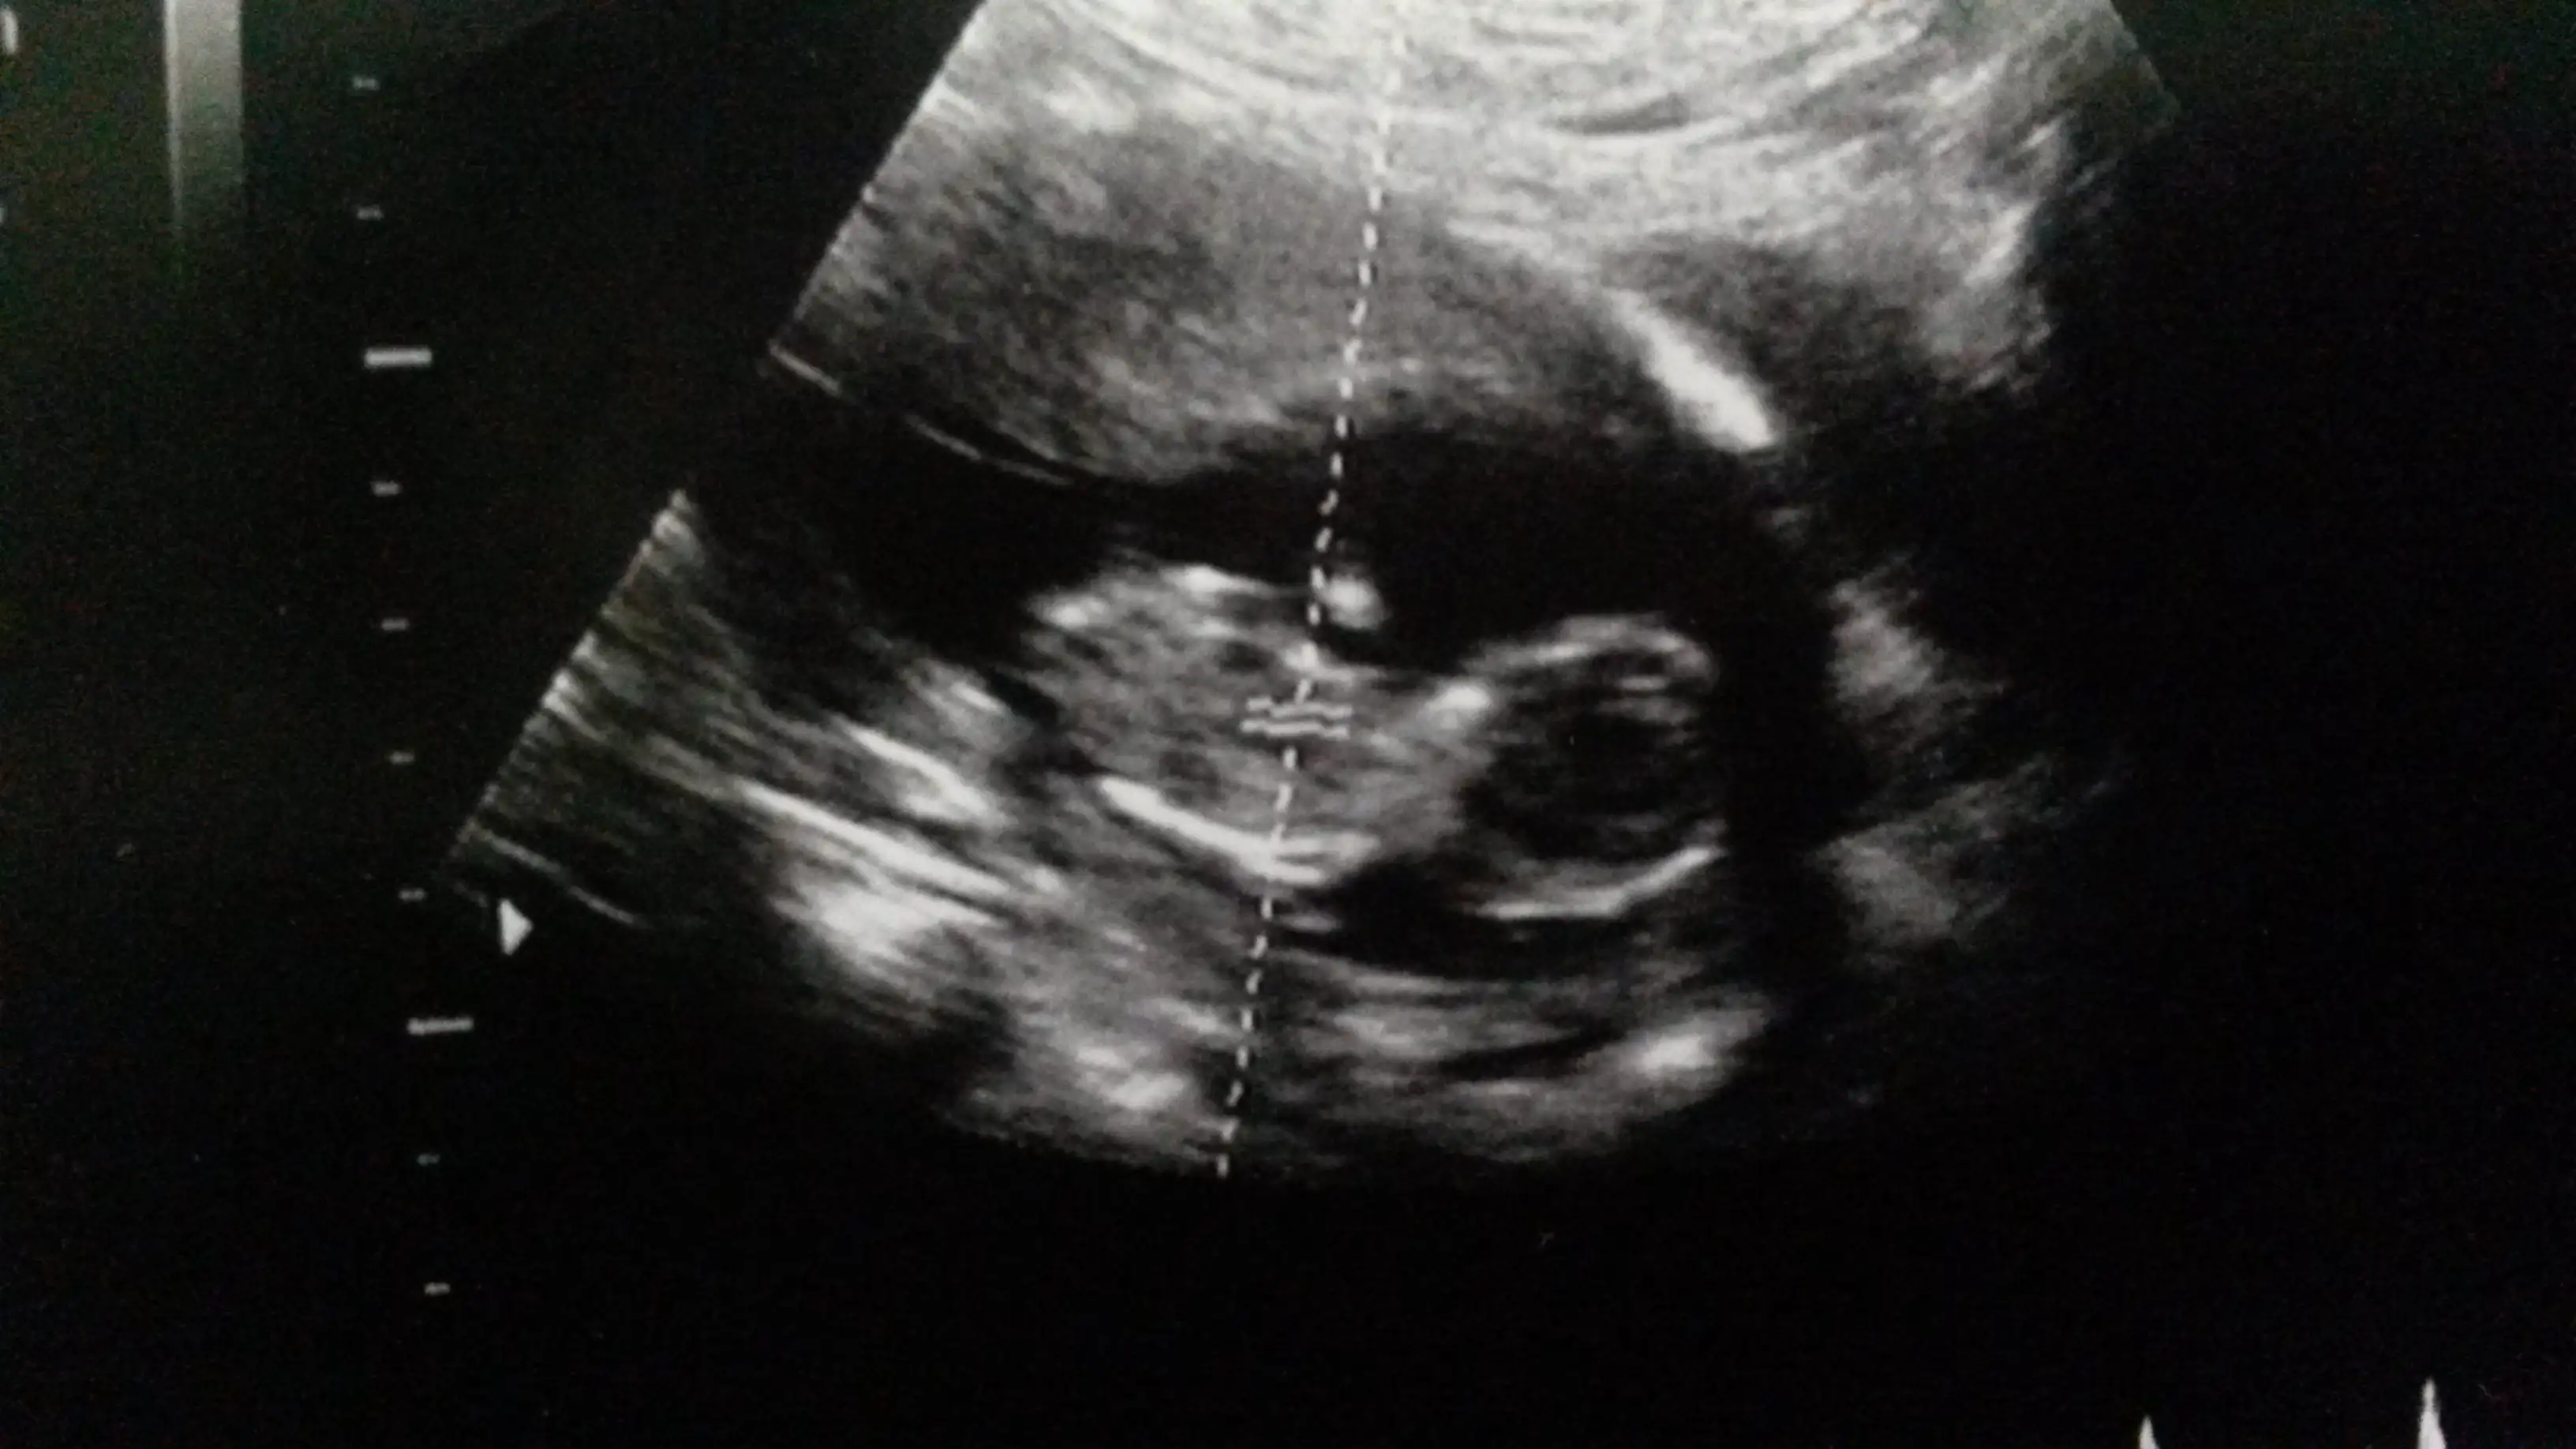

dr soylemeden siz gorun genital nub teorisi ( bebegin cinsiyeti)

Ustteki fotoda erkek gibi eger kordon degilse digerlerinde kiz gibi doktor bisey dedimi